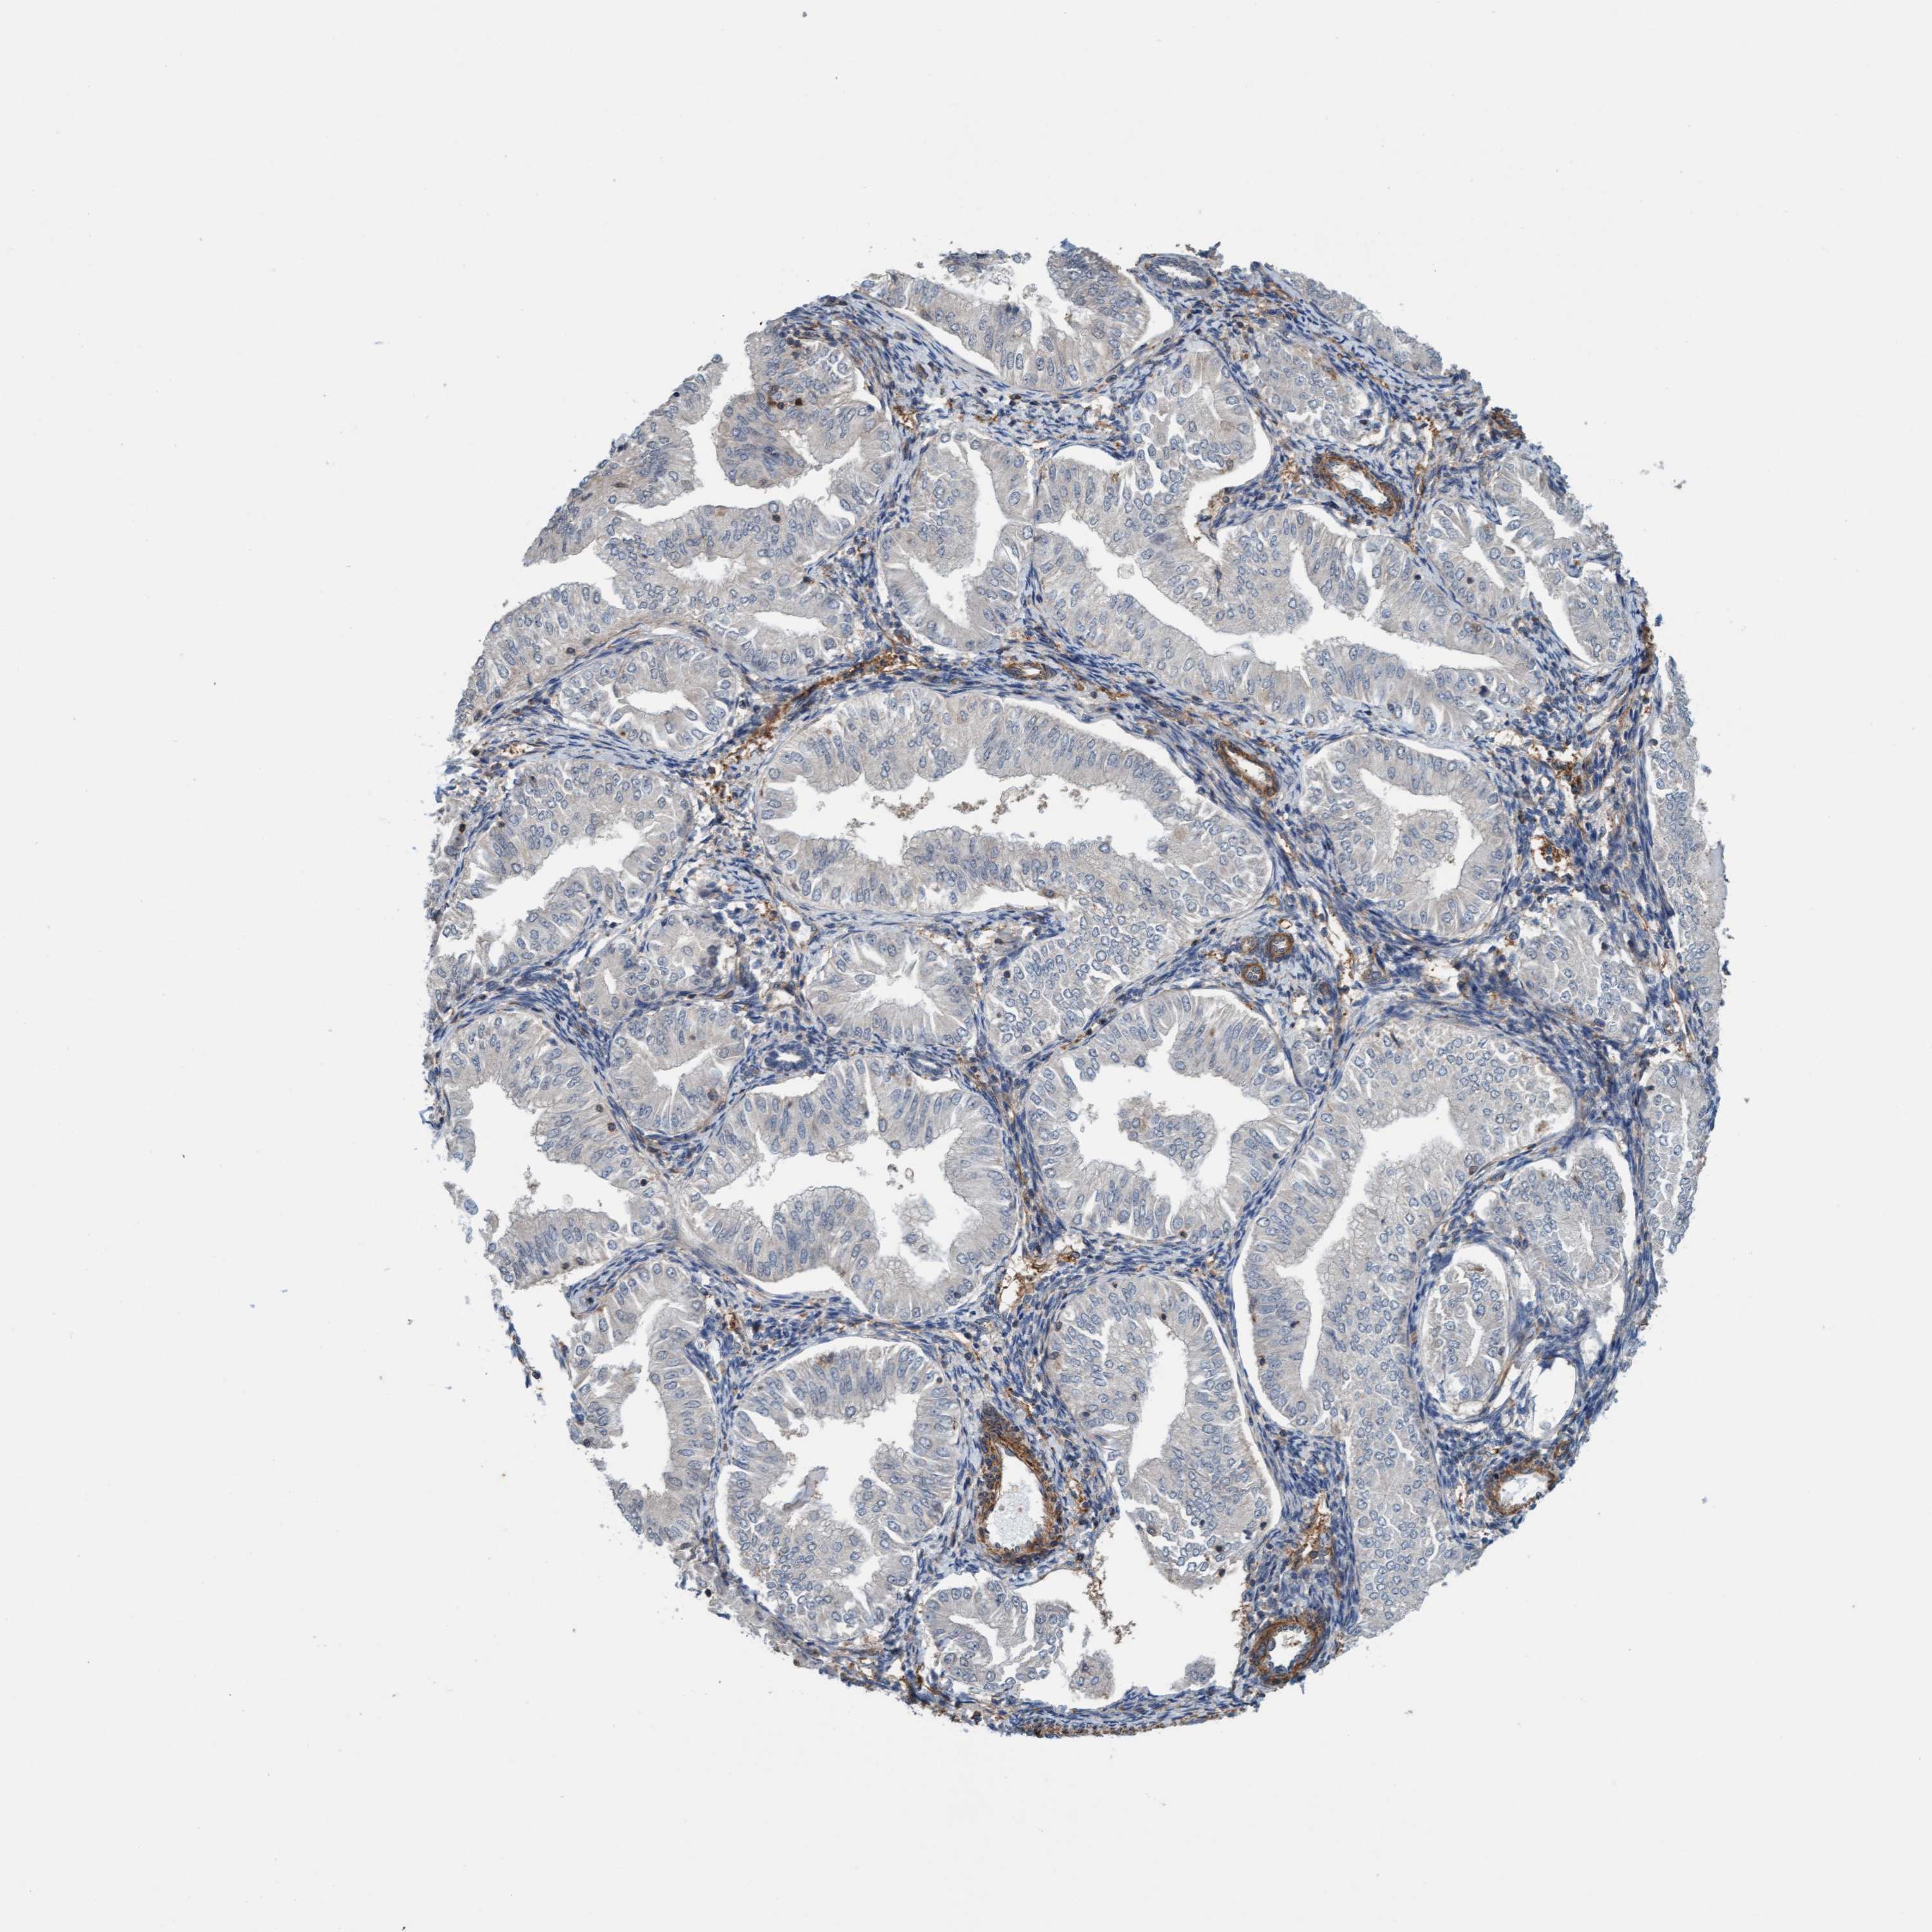

ENDOMETRIAL CANCER - Protein expressioni

A mouse-over function shows sample information and annotation data. Click on an image to view it in a full screen mode. Samples can be filtered based on level of antibody staining by selecting one or several of the following categories: high, medium, low and not detected. The assay and annotation is described here.

Note that samples used for immunohistochemistry by the Human Protein Atlas do not correspond to samples in the TCGA dataset.

Antibody stainingi

Antibody staining in the annotated cell types in the current human tissue is reported as not detected, low, medium, or high, based on conventional immunohistochemistry profiling in selected tissues. This score is based on the combination of the staining intensity and fraction of stained cells.

Each image is clickable and will lead to virtual microscopy that enables deeper exploration of all samples and also displays staining intensity scores, fraction scores and subcellular localization as well as patient and tissue information for each sample.

Antibody HPA002552

Antibody HPA023201

Staining

High

Medium

Low

Not detected

Intensity

Strong

Moderate

Weak

Negative

Quantity

>75%

75%-25%

<25%

None

Location

Nuclear

Cytoplasmic/membranous

Cytoplasmic/membranous,nuclear

Adenocarcinoma, NOS

Adenoma, NOS